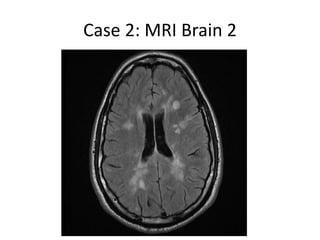

Case 2: MRI Brain 2

Case 2

• In Sept 2013, patient came with another

severe relapse , with homonymous

hemianopia, sphincteric problems, gait ataxia,

and sensory disturbance.

• Treated with pulse steroids with partial

improvement in urinary symptoms and ataxia,

but not in visual symptoms.

• MRI showed marked worsening, with

tumefactive enhancing lesions

• A CSF study was done, which was normal,

negative for JCV.

• Considering this as a failure of Tysabri, it is

planned to treat him with Rituximab